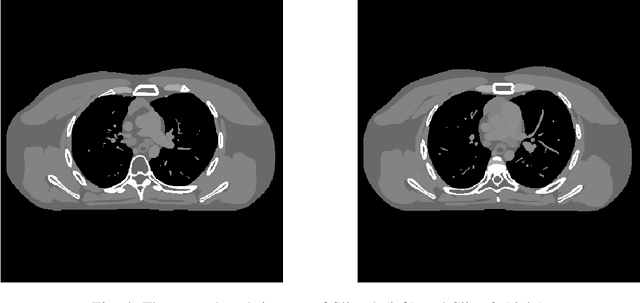

Signal models based on sparsity, low-rank and other properties have been exploited for image reconstruction from limited and corrupted data in medical imaging and other computational imaging applications. In particular, sparsifying transform models have shown promise in various applications, and offer numerous advantages such as efficiencies in sparse coding and learning. This work investigates pre-learning a multi-layer extension of the transform model for image reconstruction, wherein the transform domain or filtering residuals of the image are further sparsified over the layers. The residuals from multiple layers are jointly minimized during learning, and in the regularizer for reconstruction. The proposed block coordinate descent optimization algorithms involve highly efficient updates. Preliminary numerical experiments demonstrate the usefulness of a two-layer model over the previous related schemes for CT image reconstruction from low-dose measurements.